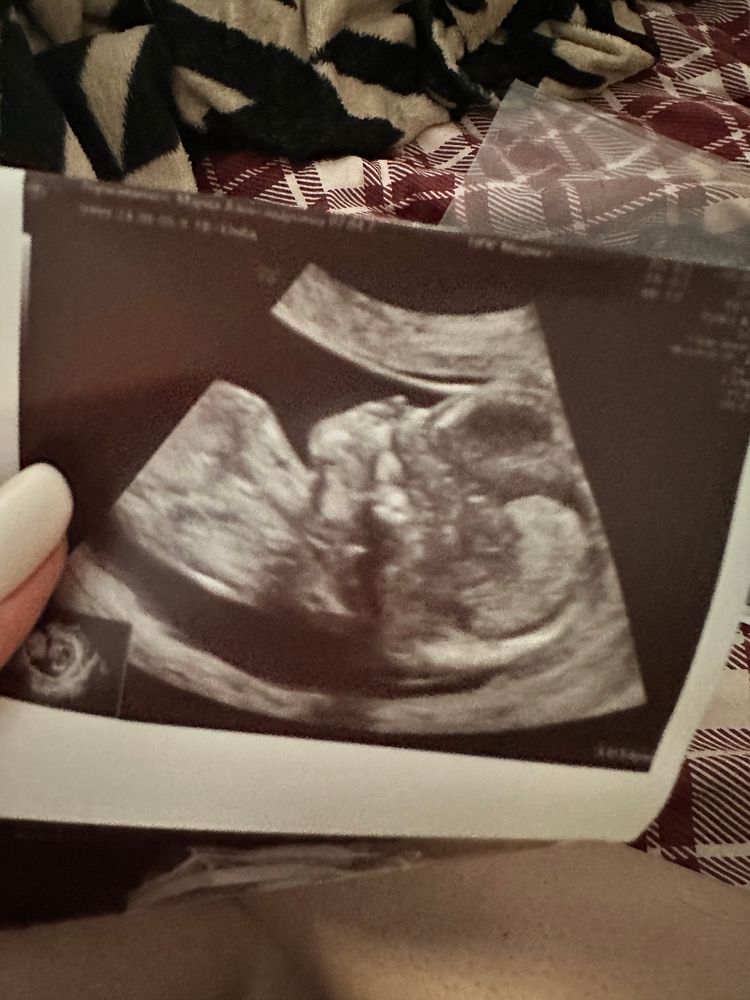

Ирина, Изображение

17.09.2024

Ирина,